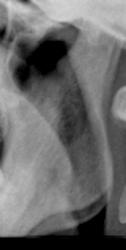

Иллюстрация 8. Область сосцевидного отростка.

Иллюстрация 9. Хорошо дифференцируется «столб воздуха».